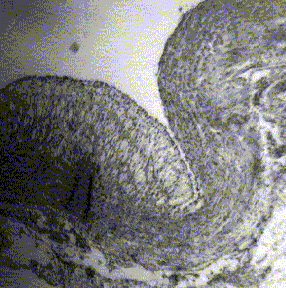

There were no consistent differences in the percentage of lesions by type among the groups (Table III). All groups, except control group (I) showed predominantly Type III (Fig. 3) and Type IV (Fig. 4) lesions.

Fig 3. Type III lesión. Foam cells surrounded by intracellular lipids of searce to moderate quantity.

Fig 4. Type IV lesion, foam cell collections with great accumulation of intra and extracellular lipids ean be observed.